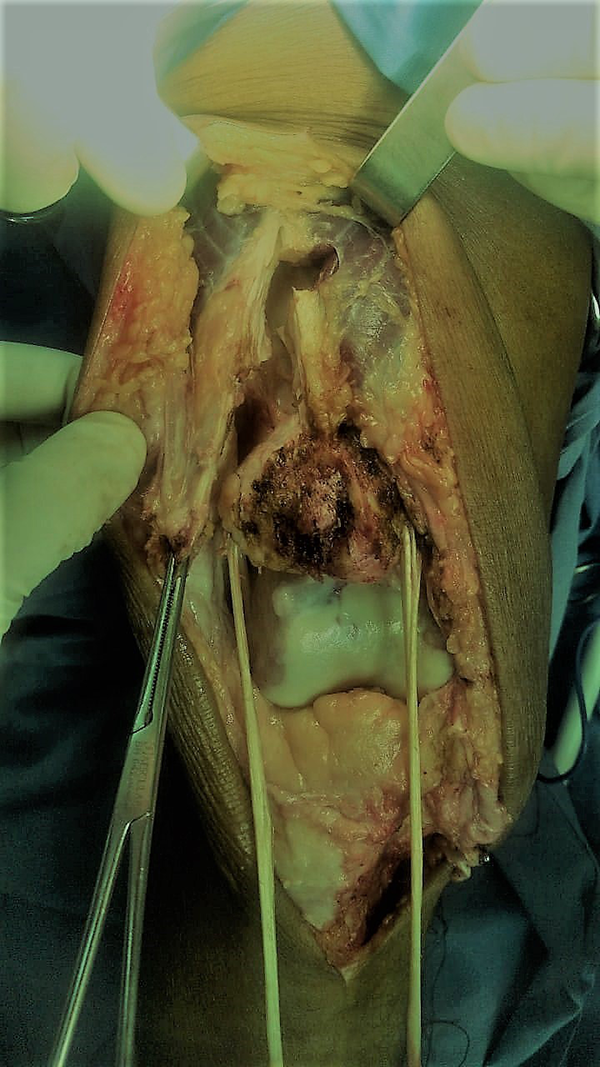

Se realiza un abordaje mediano de rodilla, divulsión hasta la lesión del tendón rotuliano y rótula. Se coloca una clavija en la zona media de la rótula en forma transversal mediante la cual se intenta su descenso, al no lograrlo, se efectúa una zetaplastia del tendón del cuádriceps más liberación del alerón externo rotuliano (fig. 4) y se logra su descenso, constatando un adecuado posicionamiento de la rótula mediante Insall-Salvatti intraoperatorio y su correcta localización en la entrada troclear a 30° de flexión de rodilla.

Figura 4: Zetaplastia del cuádriceps y liberación del alerón rotuliano externo.